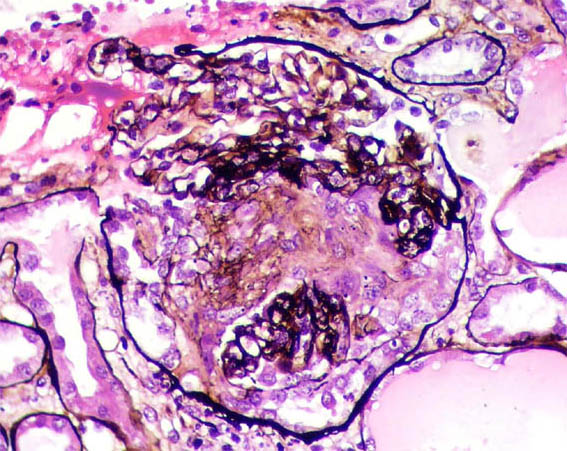

Figure 5. Methenamine-silver staining, X400.

Figure 6. Methenamine-silver staining, X400.